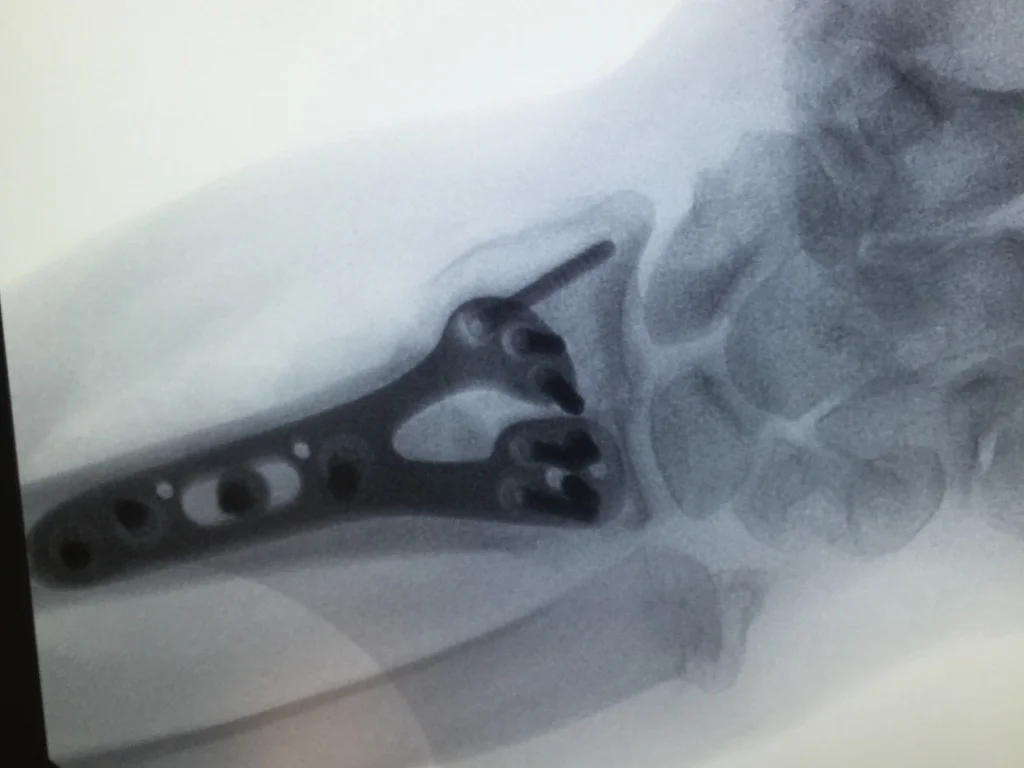

Comprehensive Orthopaedic Hand Surgery practice in Chicago's North Shore.